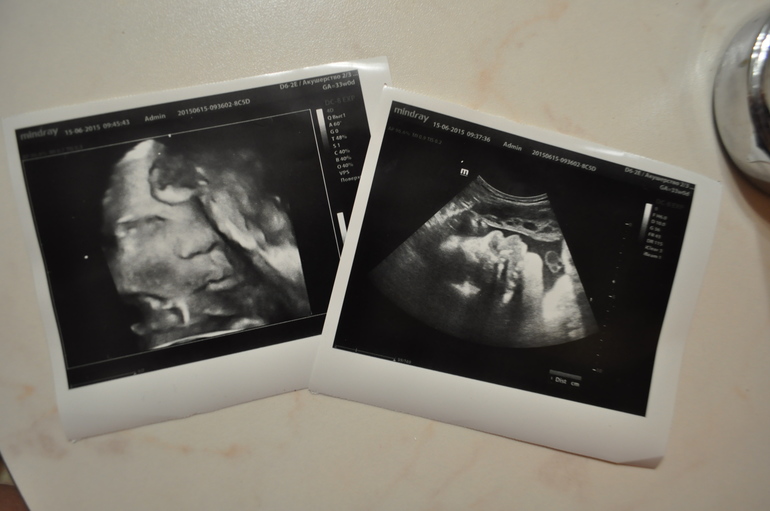

Немного позитива и фото после третьего узи =)

Наши будни, наши неделькиВсем приветик! Вот прошло третье узи и я решила наконец написать пост на память после затишья

Насмотрелись сегодня на нашу малышку, она при этом все время дубасила меня в бок

Врач сказал, что похожа на папу